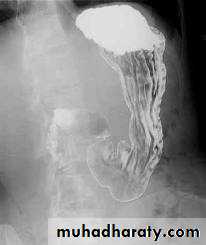

Confirmed by Ba. Swallow.

GIT